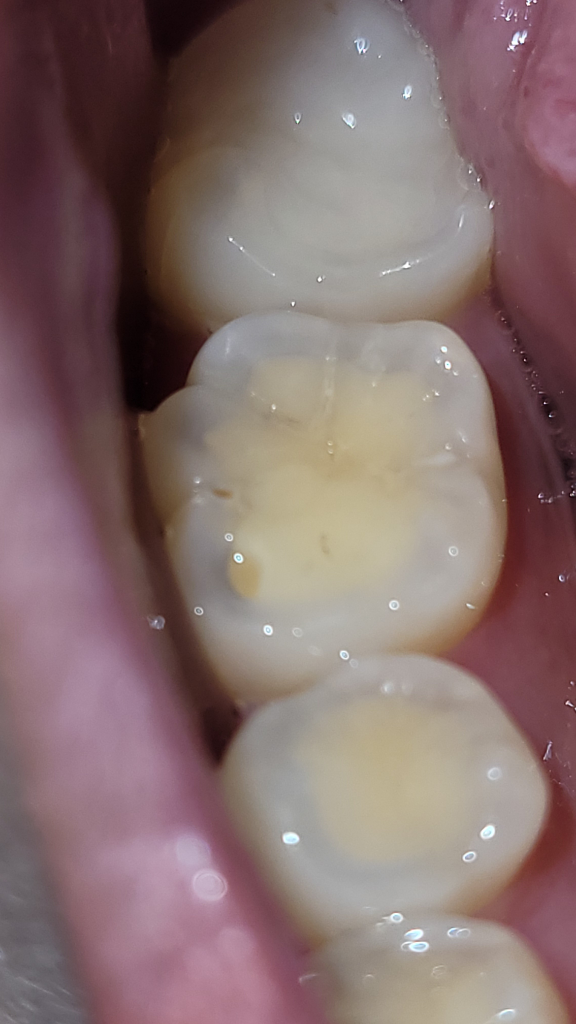

18살 때 이 어금니의 충치를 치료한 적 있는 걸로 기억합니다. 최근에 다른 이빨이 시려서 가니까 마모증이어서 레진을 하기 위해 예약을 잡아놓았는데 이번에 양치하다가 어금니 하나가 아프다는 걸 느꼈습니다. 좀 흐리지만 사진상으로 보았을 때(중간 이빨) 충치와 약간의 깨짐이 있어보이는데 혹시 어떠한 문제때문에 시림현상이 있는 걸까요? 나중에 치과갈 때 검사를 받긴 할건데 사진으로도 문제 확인이 가능한가 싶어서 여쭤봅니다.

• 1번 째 사진